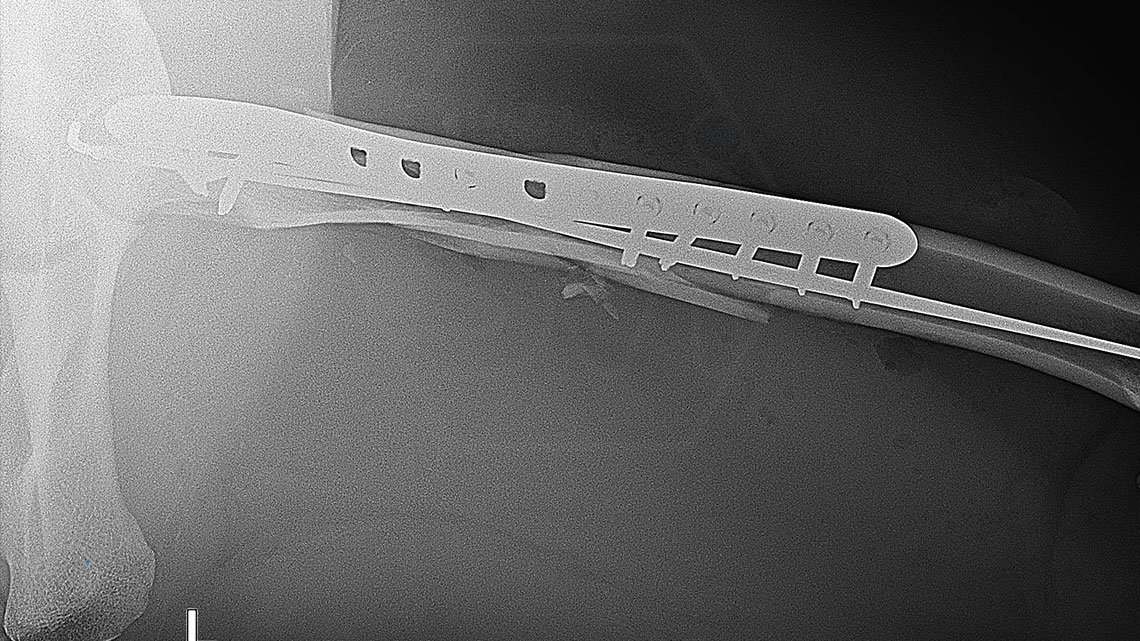

The NEW precontoured polyaxial locking TPLO plate family

07 September 2021